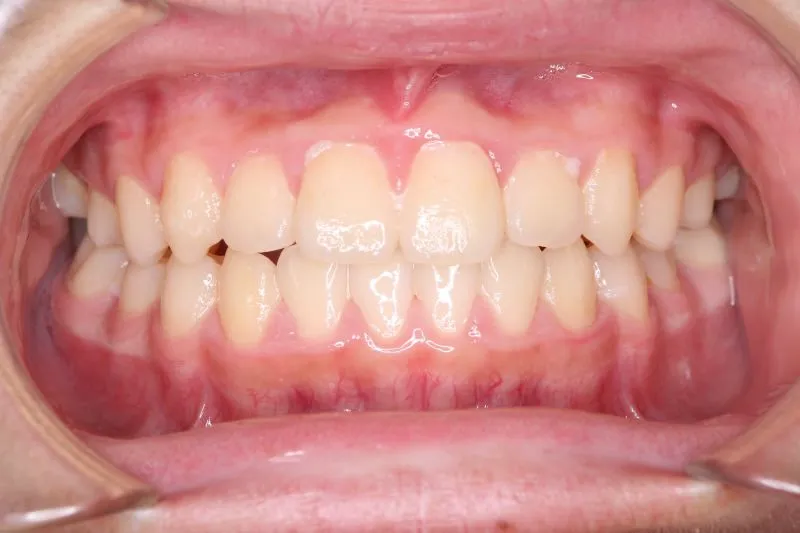

• 初診

初診時年齢 小学校3年生 (男性) 主訴 前歯の噛み合わせが悪い

診断名 切端咬合 装置名

上の歯も下の歯も歯が生えるスペースが少ない為ガタガタしています。

前歯同士が上下で付き合わせる様に噛み(切端咬合)、

その横の歯は上の歯が下の歯の後ろにきて噛んでいる状態です(反対咬合)

初診